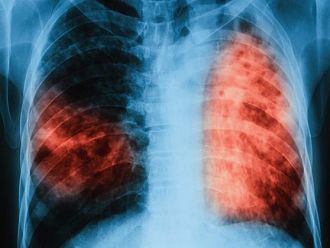

По време на „Седмицата на отворените врати“ на всеки желаещ се предлага скрининг за риска от туберкулоза чрез анкета и консултации. На лицата, които са в риск, се провеждат допълнителни прегледи и изследвания. При откриването на случаи на туберкулоза своевременно се предприемат мерки за хоспитализация и лечение, в резултат на което се прекъсва веригата за предаване на инфекцията.

По време на проведени кампании през месеците март, юни и септември 2018 г. общо анкетирани за туберкулоза са 8906 лица, на 5256 в риск от туберкулоза са извършени медицински прегледи и допълнителни изследвания. Открити са 99 лица с туберкулоза и 299 лица с латентна туберкулозна инфекция, на които е започнато лечение, отчитат от ведомството.